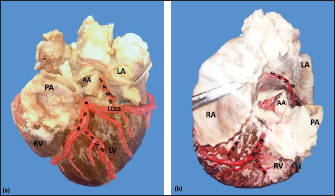

The LCA caliber and length were 9.4 ± 1.2 and 18.3 ± 4.8 mm, respectively. This artery was divided into two branches (PIB and LCXB) in 24 (85.7%) of the cases and trifurcated into PIB, LCXB, and left diagonal branch (LDB) in four (14.3%) specimens (Fig. 3). The LDB presented a caliber of 3.4 ± 0.8 mm, a length of 106.8 ± 40.3 mm, and ended in the same percentage in the upper and lower third and ended in the same percentage in the upper and lower third of the obtuse face of the heart (Table 1) (Fig. 3).

The PIB ended in 13 (46.4%) cases in the apex, followed by 42.9% in the posterior aspect of the left ventricle and to a lesser extent in the lower third of the paraconal interventricular sulcus (10.7%). The PIB presented five right branches on average and six left branches. The proximal caliber of this main arterial branch was 6.4 ± 1.4 mm, the intermediate caliber was 4.6 ± 1.1 mm, and the distal caliber was 2.9 ± 0.7 mm. Its length was 202 ± 25.2 mm (Fig. 3).

The LCXB ended in 23 specimens (82.1%) in the subsinusal interventricular sulcus and in 17.9% in the posterior aspect of the right ventricle. Its length was 149.1 ± 12.6 mm, and the calibers were as follows: proximal caliber was 5.9 ± 1.2 mm, the intermediate was 4.8 ± 0.9 mm, and the distal was 3.8 ± 0.9 mm. (Fig. 3).

The proximal calibers of the PIB and the LCXB did not present statistically significant differences (p=0.137). The length between the PIB and the LCXB presented statistically significant differences (p < 0.001), being greater in the PIB and covering more territory of the left ventricle.

Fig. 3. Left surface of the heart. Division into two branches of the LCA (*) (a); division into three branches of the LCA (b). (LA): Left atrium; (LV): Left ventricle; (RV): Right ventricle; (PA): Pulmonary artery; (PIB): Paraconal interventricular branch; (LCXB): Left circumflex branch; (LDB): Left diagonal branch; (LCB): Left cone branch; (**): Left marginal branch; (LAVB): First left anterior ventricular branch; (#):MB.